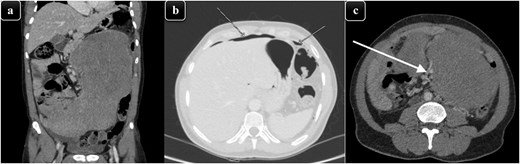

The patient was resuscitated and taken to the operating theater for an exploratory laparotomy via a midline incision with a left rooftop extension to accurately determine the mass’s extent and resectability. Upon exploration, purulent fluid was noted in the upper abdomen and left paracolic gutter, as well as a huge small bowel mesenteric mass involving the ileum and its mesentery with a perforation on the left upper side (Fig. 2). This mass was sitting on the descending colon causing proximal dilatation, but the colon itself was intact. Further dissection led to the resection of the involved small bowel and cecum along with its mesentery, leaving 170 cm of small bowel (Fig. 2). The ileocolic artery was ligated due to its anatomical course through the mass. During dissection, a small iatrogenic injury to the infrarenal abdominal aorta and to the proximal jejunum occurred; both injuries were repaired primarily. In addition, the right ureter was transected due to its proximity to the mass and was repaired primarily over a DJ stent. The abdomen was irrigated and left open for a second-look laparotomy involving vascular and urology teams.

(a) An intra-operative image illustrating the mass that originated from the mesentery along with small bowel adhesion and perforation within the tumor. (b) Specimen image showing the excised well-circumscribed lesion with a smooth external surface along with a portion of the small intestine and its mesentery that was involved.